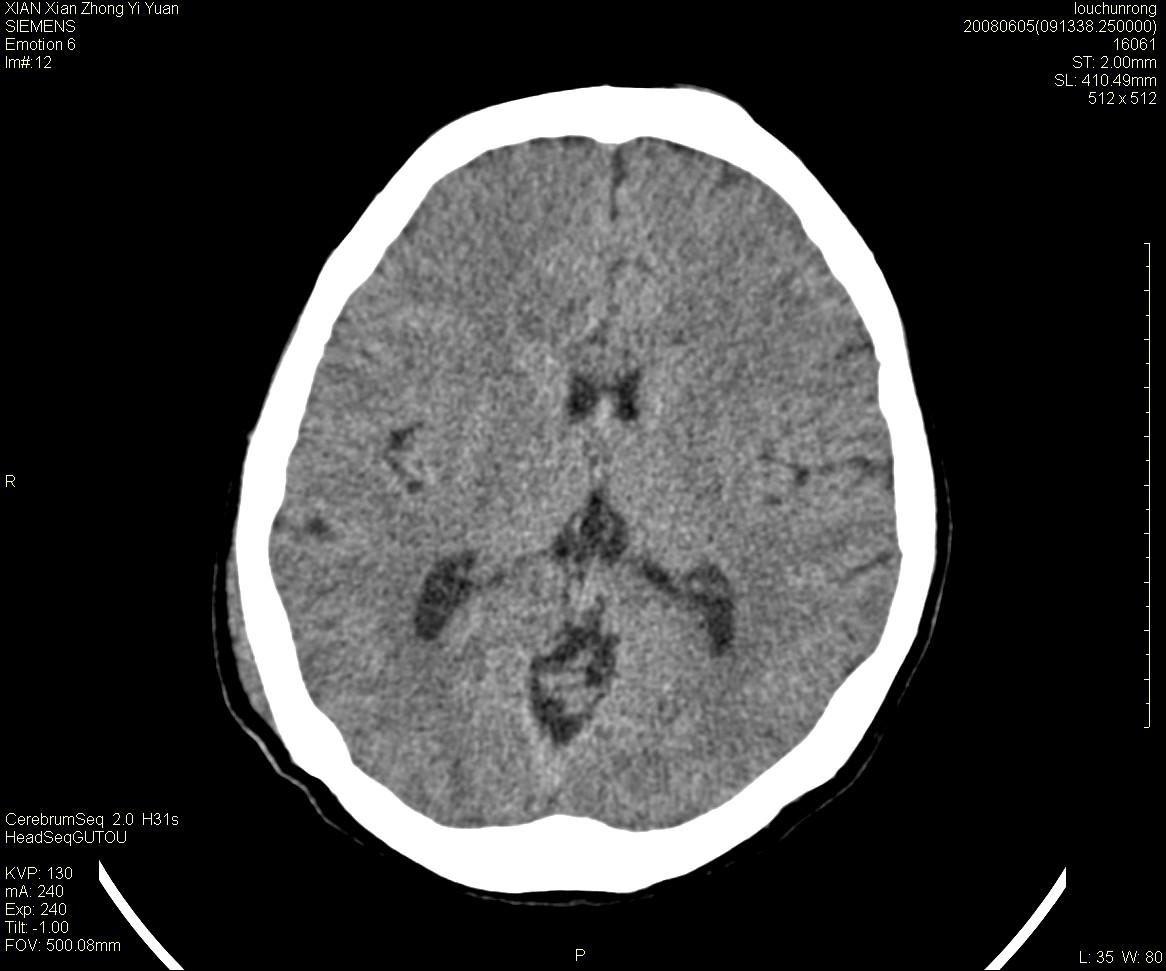

标题: CT13860:F52Y,,头外伤致头晕半天,以前无不适。 [打印本页]

标题: CT13860:F52Y,,头外伤致头晕半天,以前无不适。

层厚2mm。

静脉窦血栓? mri检查

大家看左额叶大脑镰旁高密度影

中线附近、枕叶近枕骨处及脑内多发点条状强化影,考虑血管异常?